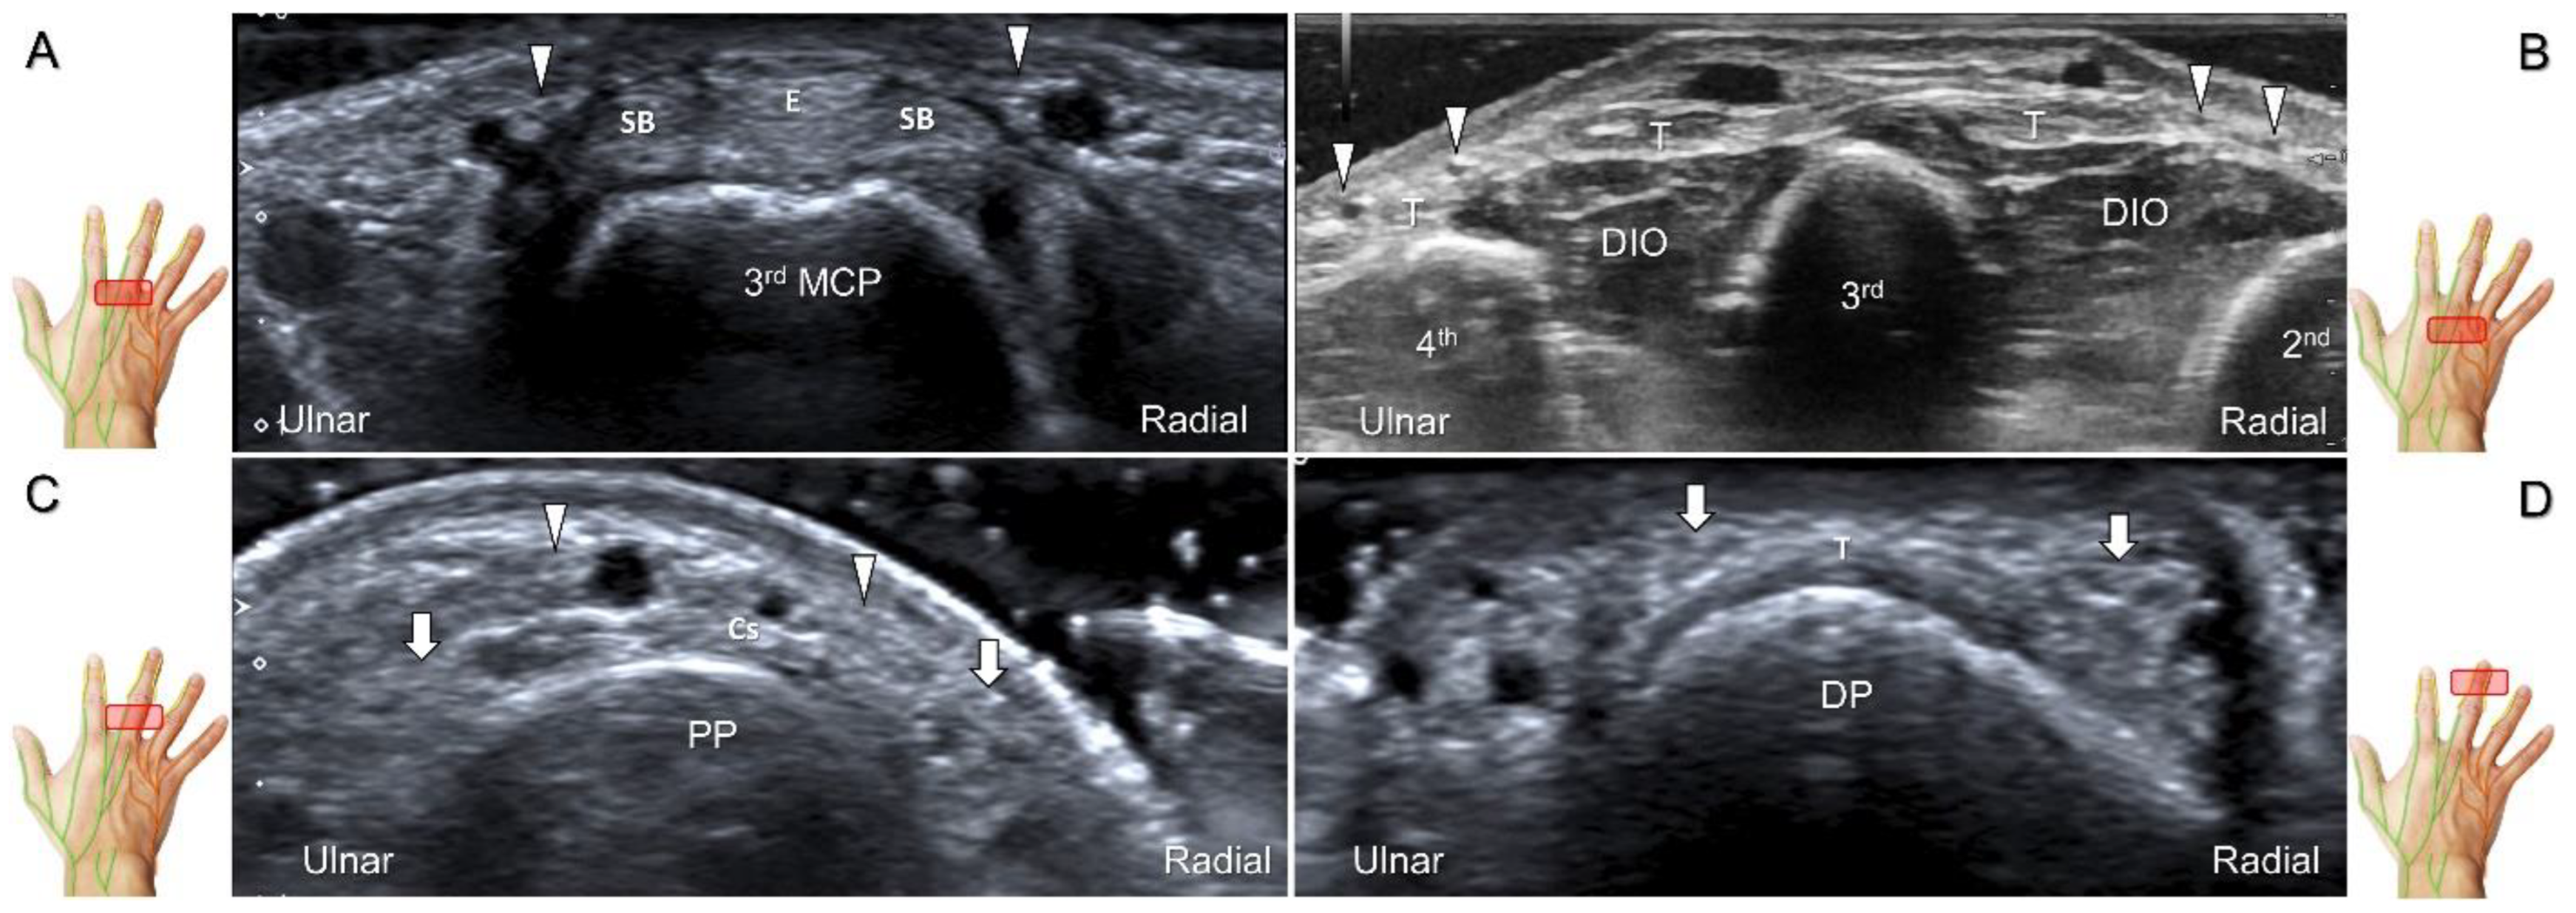

Scanning Technique

The transducer is positioned on the axial plane of the dorsal metacarpal joint in the target digit. The dorsal proper digital nerves can be found on either side of the sagittal band (Figure 33A). The transducer is moved proximally and the dorsal common digital nerves can be observed superficial to the extensor (usually the extensor digitorum proprius) tendons (Figure 33B). By returning to the level of the sagittal band and moving the transducer distally, the dorsal proper digital nerves can be seen superficial to and alongside the central slip of the finger extensor tendon (Figure 33C). Alternatively, moving the transducer distally toward the proximal phalanx of the first to the radial aspect of the fourth phalanx allows observation of the nerve fascicles of the palmar proper digital nerve originating from the median nerve (Figure 33D).

Figure 33. Sonographic imaging of the dorsal common digital nerve on the metacarpal bone (A), toward the metacarpal head (B). Dorsal proper digital nerves on the proximal phalanx (C), and the terminal nerve originating from the palmar proper digital nerve on the distal phalanx of third finger (D). Arrowheads: dorsal common digital nerve; arrows: palmar proper digital nerve. MCP: metacarpal bone; SB: sagittal band; E: extensor tendon; Cs: central slip; PP: proximal phalanx; T: terminal band; DP: distal phalanx; DIO, dorsal interosseous muscle.